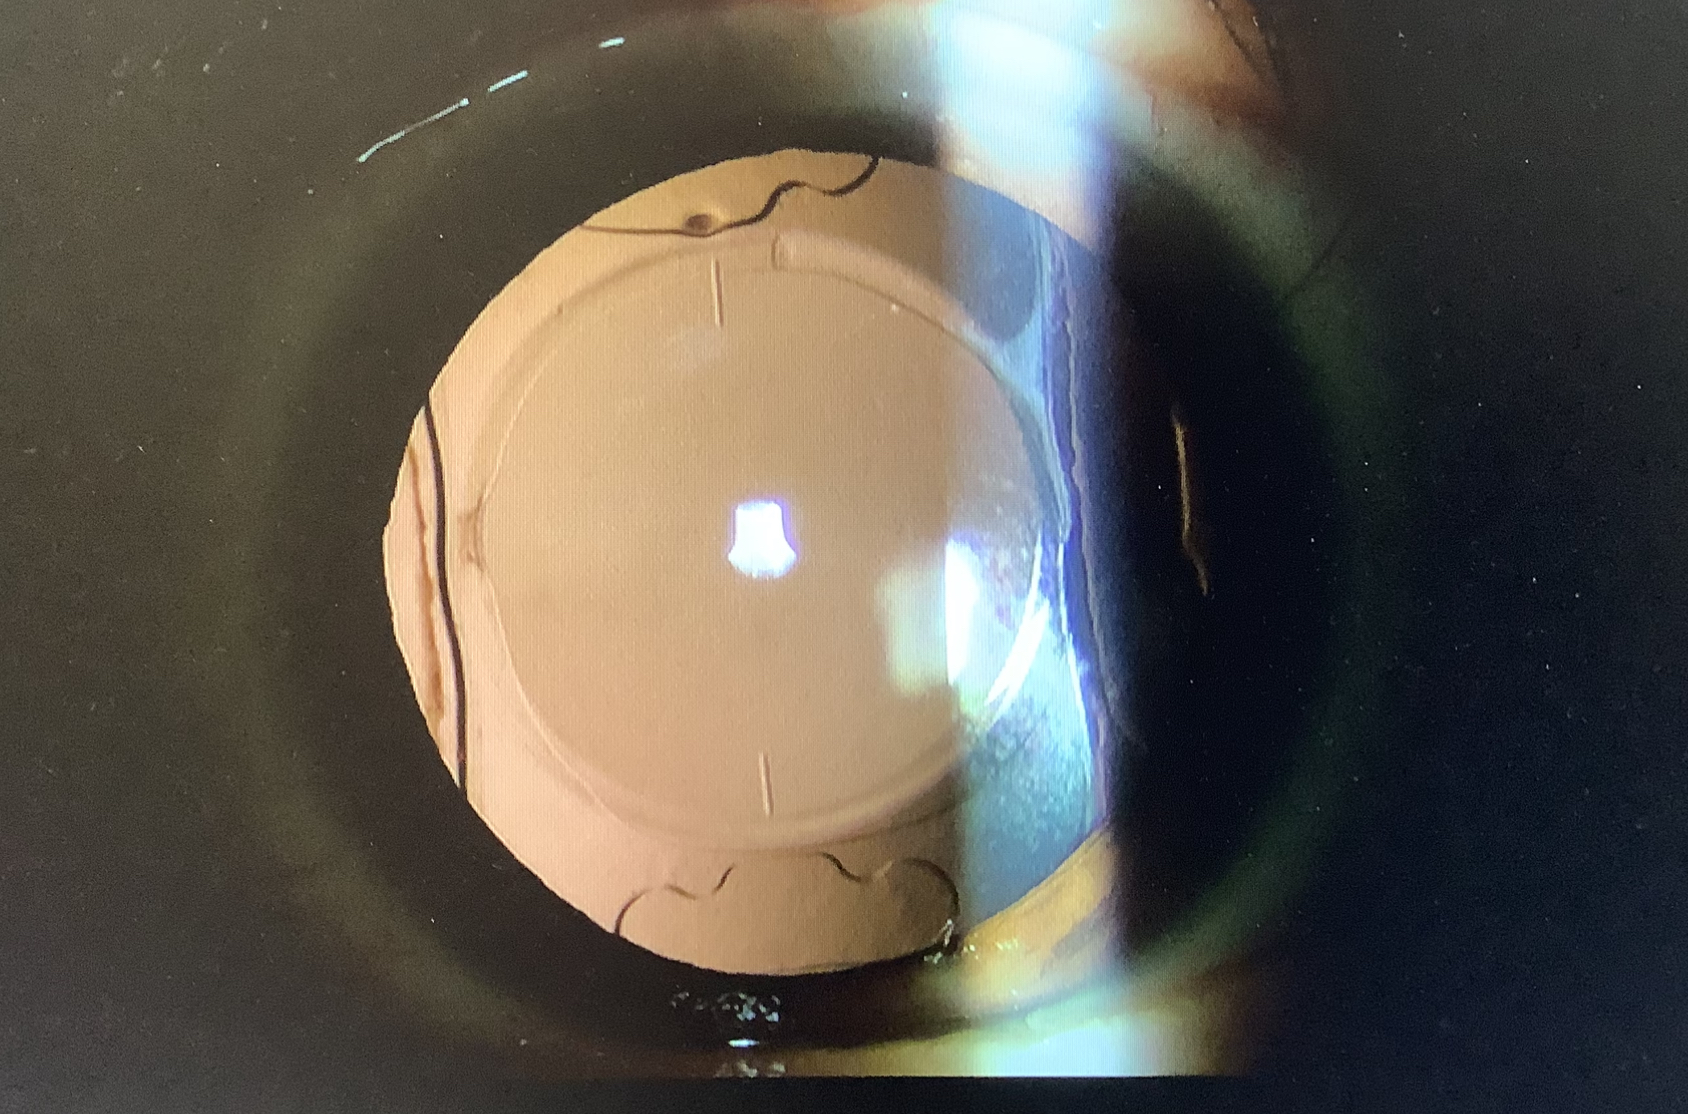

今日の入れ換え相談は50代前半の女性で他院で6月に両眼の白内障手術を受け、レンティスコンフォートを左右で少し差をつけて入れたところ、『鮮明に見えない、横から入る光が眩しい、ギラギラして見えにくい』という症状で困ってしまったそうです。

左右差は1Dほどで、極端には大きくなく、レンティスではあまり問題にならない差かなと思いますが、実際、前医でコンタクトレンズを使い左右差を消して見え方を試したところ、はっきりは見えなかったそうで、おそらく見えにくさの原因としては、レンズの構造によるものと思われました。